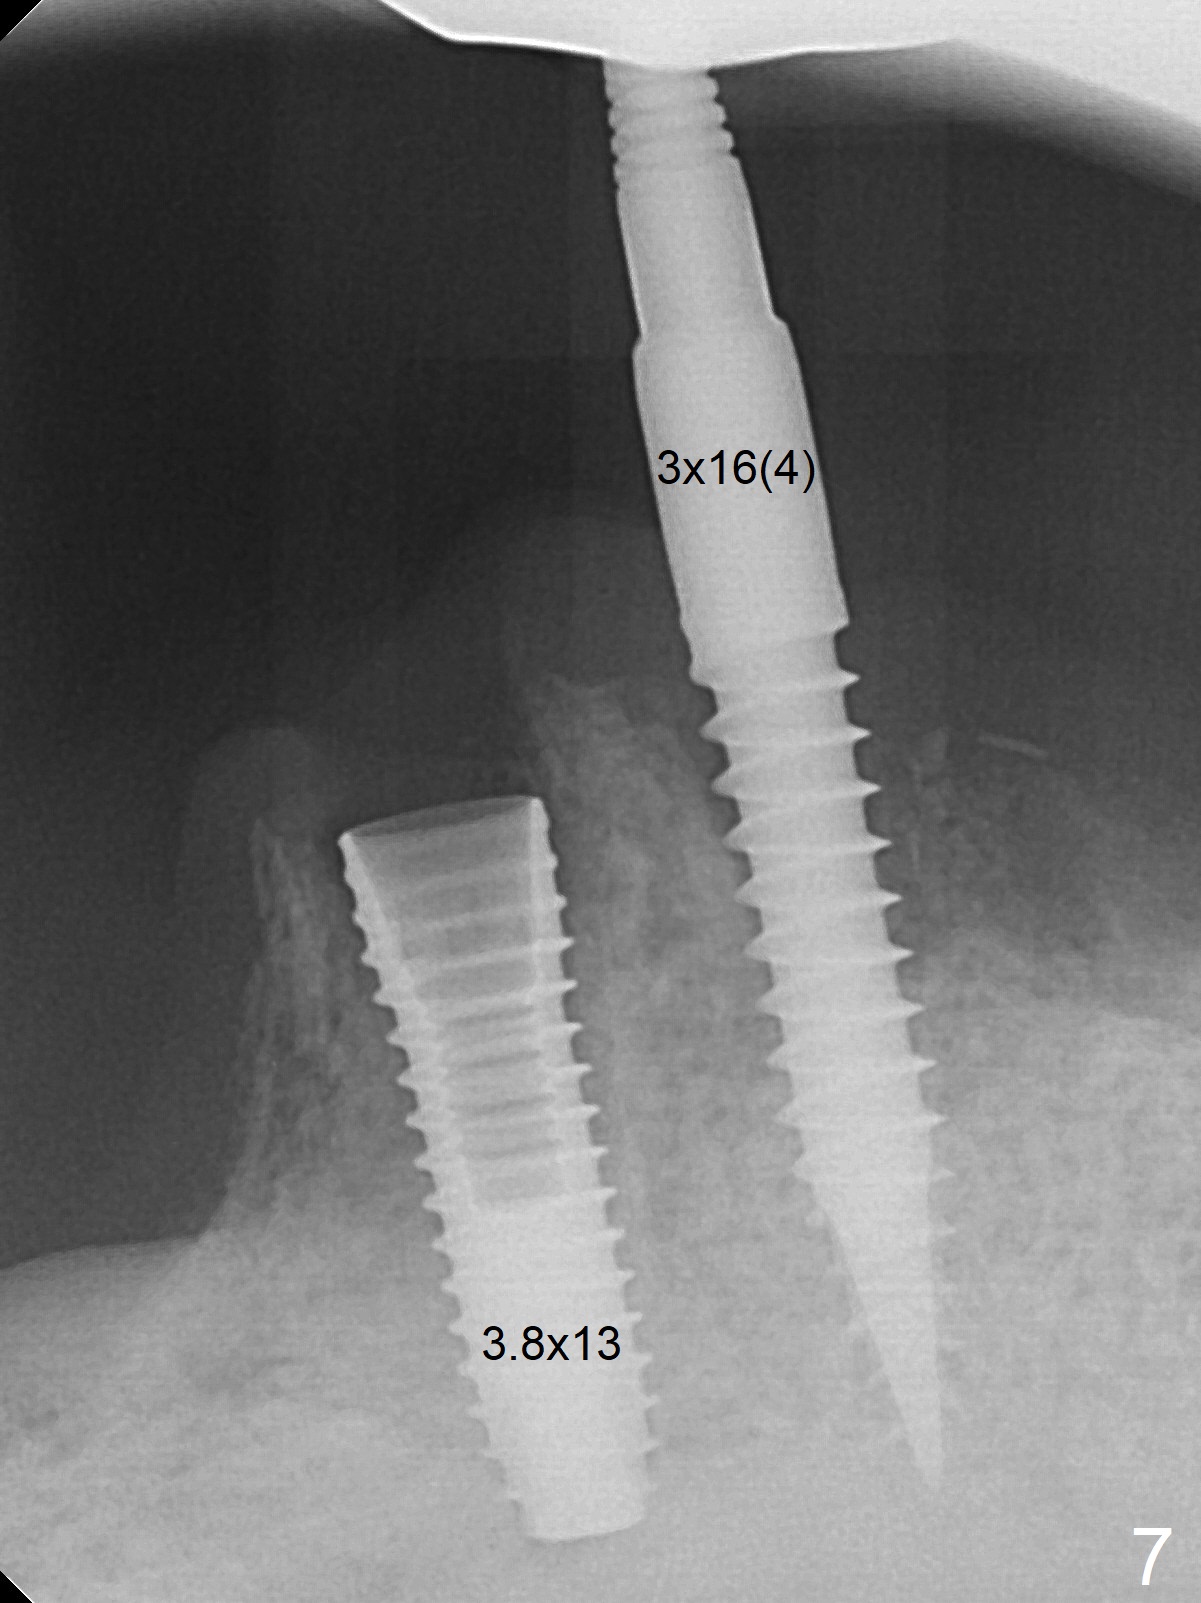

When the patient returns for #26 extraction and immediate implant and #27 RCT, it appears that the tooth #27 with subgingival margin distolingually is non-salvageable (Fig.1). She has dry mouth. Osteotomy is initiated in the lingual slope (Fig.4 red dashed line) of each socket with 1.2 and 2 mm drills for 16 and 19 mm at #26 and 27, respectively (Fig.2,3). The depth at #27 is subsequently reduced, while a 3x14(2) mm dummy implant is placed at #26 (Fig.5,6). A 3.8x13 mm implant is placed at #27 smoothly, while insertion of a 3x16(4) mm definitive implant (by mistake) has resistance (Fig.7). When the depth at #26 increases, there is feeling of perforation. The apex of the implant is truncated prior to reinsertion (Fig.8 >).